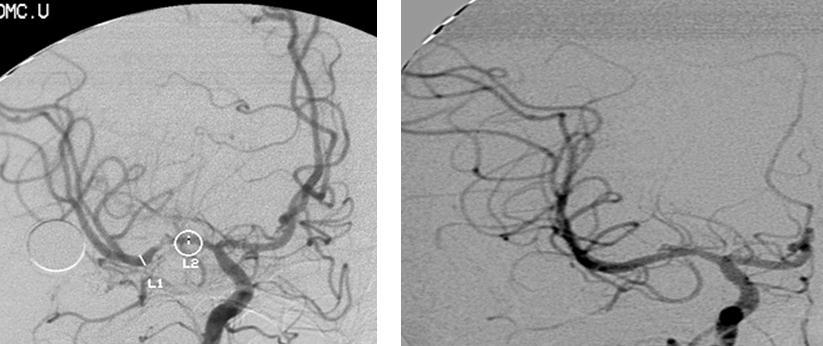

A twenty-nine-year-old female was admitted in Feb, 2006 because of episodic left limb numbness and weakness for half a year. The duration of the episode lasted for a few minutes, seldom over ten minutes. There was an attack every several days. She denied special medical history. She did not live in the pandemic area of Leptospirosis. Her blood pressure was 110/65mmHg and body weight was 51 kilograms. Physical examination found no abnormality. Magnetic resonance angiogram (MRA) (Feb 22) showed severe stenosis in the M1 segment of right MCA. In the source images of MRA, an oval area of abnormal signal in the right basal ganglion was found (Figure 1). Blood routines, coagulation tests, blood biochemistry tests, and C-reactive protein level were normal. The anti-nuclear antibody (ANA), anti-extractable nuclear antigen (ENA) antibodies, and anti-neutrophil cytoplasmic antibodies (ANCA) were negative. Serologic test for Syphilis was negative. Blood sedimentation rate (ESR) was 20 mm/h, and the level of anti-streptolysin O microtitration test (ASO) was 395 IU/ml (0-200 IU/ml). Digital subtraction angiography (DSA) detected severe stenosis (95%) in M1 segment of the right MCA, and the distal blood flow was compromised (Figure 2). The patient was given aspirin 100mg/d, clopidogrel 75mg/d and atorvastatin 20mg/d since Feb 26. Due to the finding of high ASO level, she was given penicillin (4 million IU, bid) for a week. Because of disagreement between the consulting physician and the interventional radiologist, her angioplasty and stenting was delayed till Mar 21 on her request. During the waiting time, her attacks did not reduce. Before the operation, besides the combination of aspirin and clopidogrel, subcutaneous low molecular weight heparin (LMWH) (5000U, q12h) was given for 5 days. After a complete diagnostic evaluation of the blood vessels with DSA, stenting was performed with a stainless steel stent 2.75 mm in diameter by 1.5 cm in length (PC, Abott Company) at the presure of 7 atm. No compromise of perforating branches was found and residual stenosis was less than ten percent on angiography (Figure 2).

Figure 2.Right MCA before and after angioplasty and stenting